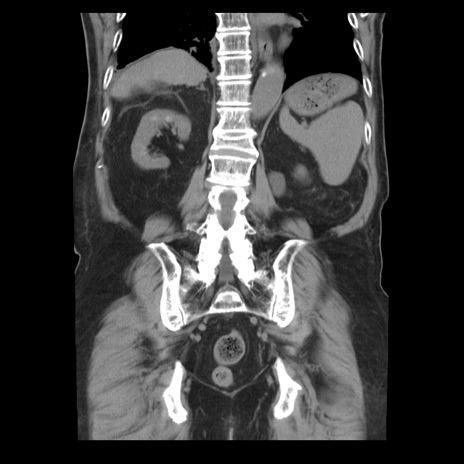

横断像

【症例】70歳代男性

【主訴】腹痛

【現病歴】肝硬変・肝細胞癌にてかかりつけの方。約9時間前に食後より腹痛出現。症状が徐々に増悪し、嘔吐出現したため来院。

【既往歴】肝硬変、肝細胞癌(RFA、TACE後)

【身体所見】意識清明、表情苦悶様、BT 36℃、BP 129/78mmHg、P 88bpm、SpO2 97%(RA)、右上腹部から心窩部にかけて圧痛あり、反跳痛なし、筋性防御あり。

【データ】WBC 5800、CRP 0.16